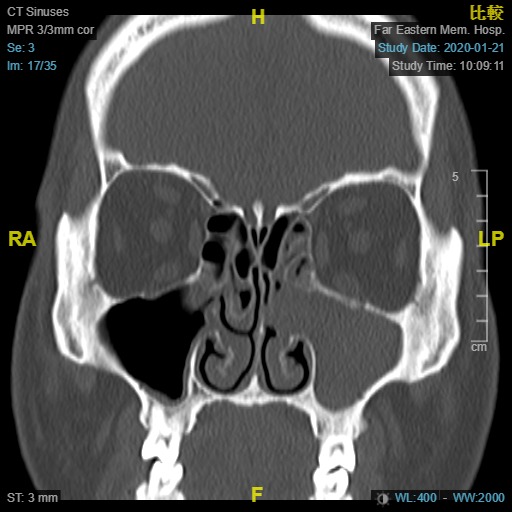

左側鼻竇炎之電腦斷層檢查,左側上頷竇異常